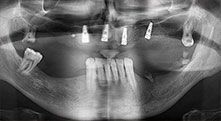

El Dr. Emanuel Bratu, catedrático con doble doctorado, es cirujano oral, cirujano maxilar y protésico y dirige los departamentos de implantología de dos universidades en Rumanía. Además, es el propietario de una reputada clínica privada en Timisoara y también se le considera una autoridad internacional en el campo de la investigación. En la entrevista, el Dr. Bratu explica las razones por las que el equipo piezoquirúrgico Piezomed de W&H y, en particular, sus dos sierras patentadas, se han convertido en elementos imprescindibles en las intervenciones óseas que se llevan a cabo en el campo de la odontología.

Bratu: Utilizamos los insertos de forma rutinaria para la extracción de injertos óseos y la ranuración de las crestas alveolares. También utilizamos las Piezomed B6/B7 para practicar osteotomías en dientes retenidos y no retiramos implantes que pueden conservarse. Todas estas son indicaciones que requieren cortes profundos y limpios.

Bratu: Preferimos realizar las osteotomías en la línea oblicua externa de la cara posterior del maxilar inferior, y no en la región situada entre los orificios. Tras realizar una incisión en los tejidos blandos, utilizamos las nuevas sierras para definir el contorno de la osteotomía. De este modo, conseguimos una preparación completa en prácticamente el 80 por ciento de los casos. Por otro lado, en algunas ocasiones también utilizamos otros insertos piezoquirúrgicos, así como un cincel para mover el injerto. Para nosotros, esta es una técnica de intervención muy eficaz.